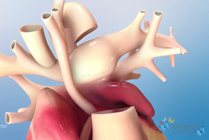

Hypoplastic Left Heart Syndrome

Hypoplastic left heart syndrome (HLHS) is a congenital heart defect where most of the structures on the left side of the heart are small and underdeveloped. The Hybrid approach, developed by surgeons at Nationwide Children's Hospital, is an alternative to Norwood open heart surgery for HLHS.